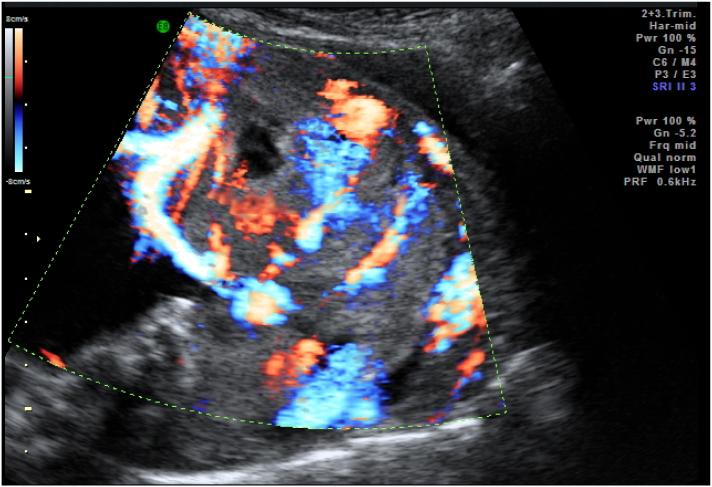

Placenta accreta spectrum (PAS) is a state of abnormal attachment of the placenta, including placenta accreta, placenta increta, and placenta percreta. This condition can be life-threatening due to the placenta cannot spontaneously separated, resulting in continuous bleeding. Cesarean section followed by hysterectomy is one of the treatment options for PAS. There was a great liability for urinary tract injuries during the operation of PAS patient.

胎盘植入谱系疾病(PAS)是胎盘异常附着的一种状态,包括胎盘粘连、胎盘植入和穿透性胎盘植入。由于胎盘无法自然剥离,这种情况可能会危及生命,导致持续出血。剖宫产加子宫切除术是PAS的治疗选择之一。在PAS患者手术过程中,尿路损伤的风险很大。